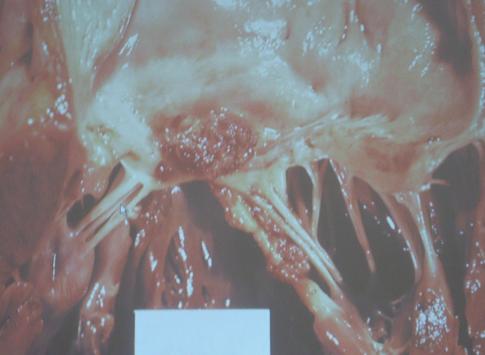

本来、心内膜というものは、ツルッとしていますが、心臓内の異常な血液の流れで

「弁」に目に見えないくらいの小さな傷ができる場合があります。

そのバイ菌が集まって、「疣腫(ゆうしゅ) vegetation」(=いぼ状の感染巣) となり

「弁」が破壊されていきます。

すると、穴が空いた状態になってしまい、逆流を防ぐことができないので

血液が常に逆流するような状態が生まれるということになります。